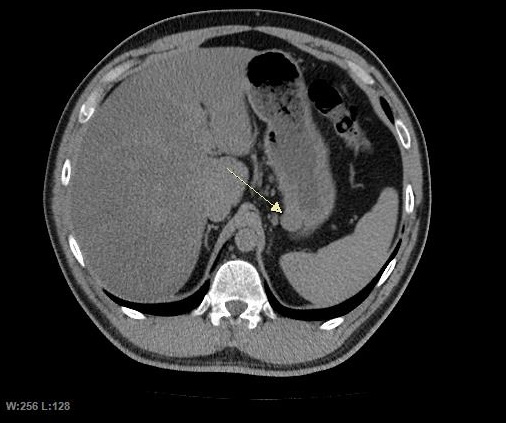

CT 스캔과 MRI는 GIST를 평가하는 데 선호되는 영상 검사 방법이다. 작은 GIST는 대개 점막하 종양 또는 장벽 내 종괴로 나타난다. 바륨 연하 검사에서 이러한 GIST는 인접한 장벽과 직각 또는 둔각을 이루는 매끄러운 경계로 나타나며, 점막 표면은 대개 손상되지 않지만, 50%에서 궤양이 나타나기도 한다. 궤양은 바륨으로 채워져 과녁 또는 표적 병변처럼 보인다. 조영 증강 CT에서 작은 GIST는 균질한 감쇠를 보이는 매끄럽고 선명하게 정의된 장벽 내 종괴로 보인다.큰 GIST는 장 밖으로 튀어나오거나 장 내부로 성장할 수 있으며, 내부에서 괴사(죽음)하여 결국 장 내강과 소통하게 될 수 있는 공동을 형성한다. 공동 형성이 있는 경우, 단순 방사선 촬영에서 종양 내 공기 덩어리가 나타날 것이다. 석회화는 GIST의 드문 특징이지만, 존재할 경우 단순 촬영에서 볼 수 있다.

악성 GIST는 국소 침윤과 전이를 특징으로 하며, 전이는 주로 간, 대망, 복막으로 발생한다. 그러나 뼈, 흉막, 폐, 후복막으로의 전이 사례도 보고되었다. 위 선암종 또는 위/소장 림프종과 달리, 악성 림프절병증 (부어오른 림프절)은 드물며 (<10%) 따라서 영상 검사에서는 림프절 비대가 없는 경우가 많다. 전이가 없는 경우, 악성을 시사하는 다른 방사선학적 특징으로는 크기 (>5 cm), 조영제 투여 후의 불균일한 조영 증강 및 궤양이 있다.[12]